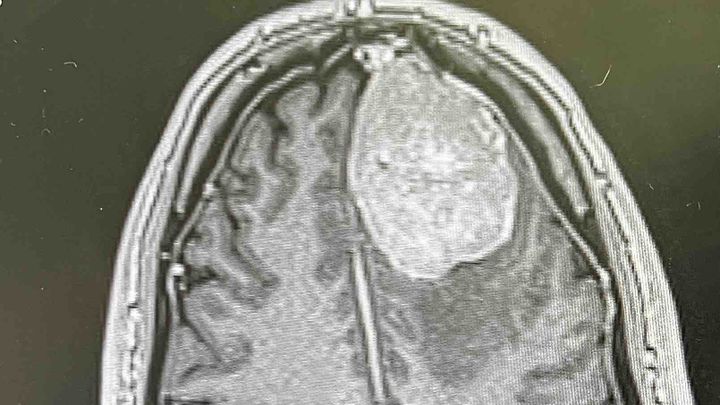

Once in the hospital I was given an MRI where

the neurological team fond a 5x4x4 cm tumor growing inside my left frontal lobe with current blood flow.

The pressure has been extensive and is around 15-20 years old according to the bruised aera and size on the scan.

The mass is not cosmetic or something that can be left untreated. It must have action taken now for my health. .

I have a tumor the size of a small lime to a tennis ball pressing on my left frontal lobe that must come out and I need some confidence it will come out.